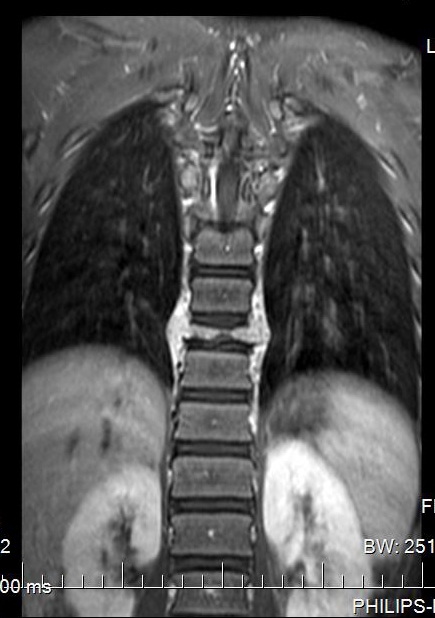

胸椎MRI平扫+增强扫描:第9胸椎椎体及其周围软组织感染性病变,并第9胸椎椎体病理性骨折。以结核性感染可能性大。

MRI

椎体脊柱病变可单发或多发,椎体可呈楔形或完全变扁呈钱币状,亦可呈溶骨性破坏,很少累及相邻的椎体椎间隙。CT及MRI可多层面显示椎体及附件的溶骨性破坏椎体的溶骨性破坏。常累及一侧椎弓根,同时还可清楚显示椎旁的软组织肿胀和包块,亦可显示椎管内受累的情况。